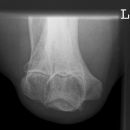

Ellenbogen seitlich (2. Ebene radio-ulnar)

Indikation

Qualitätskriterien

Ellenbogengelenk vollständig seitlich orthograd abgebildet. Humeroulnar Gelenkspalt einsehbar. Humeruskondylen müssen sich decken, das Radiusköpfchen soll gut beurteilbar sein.